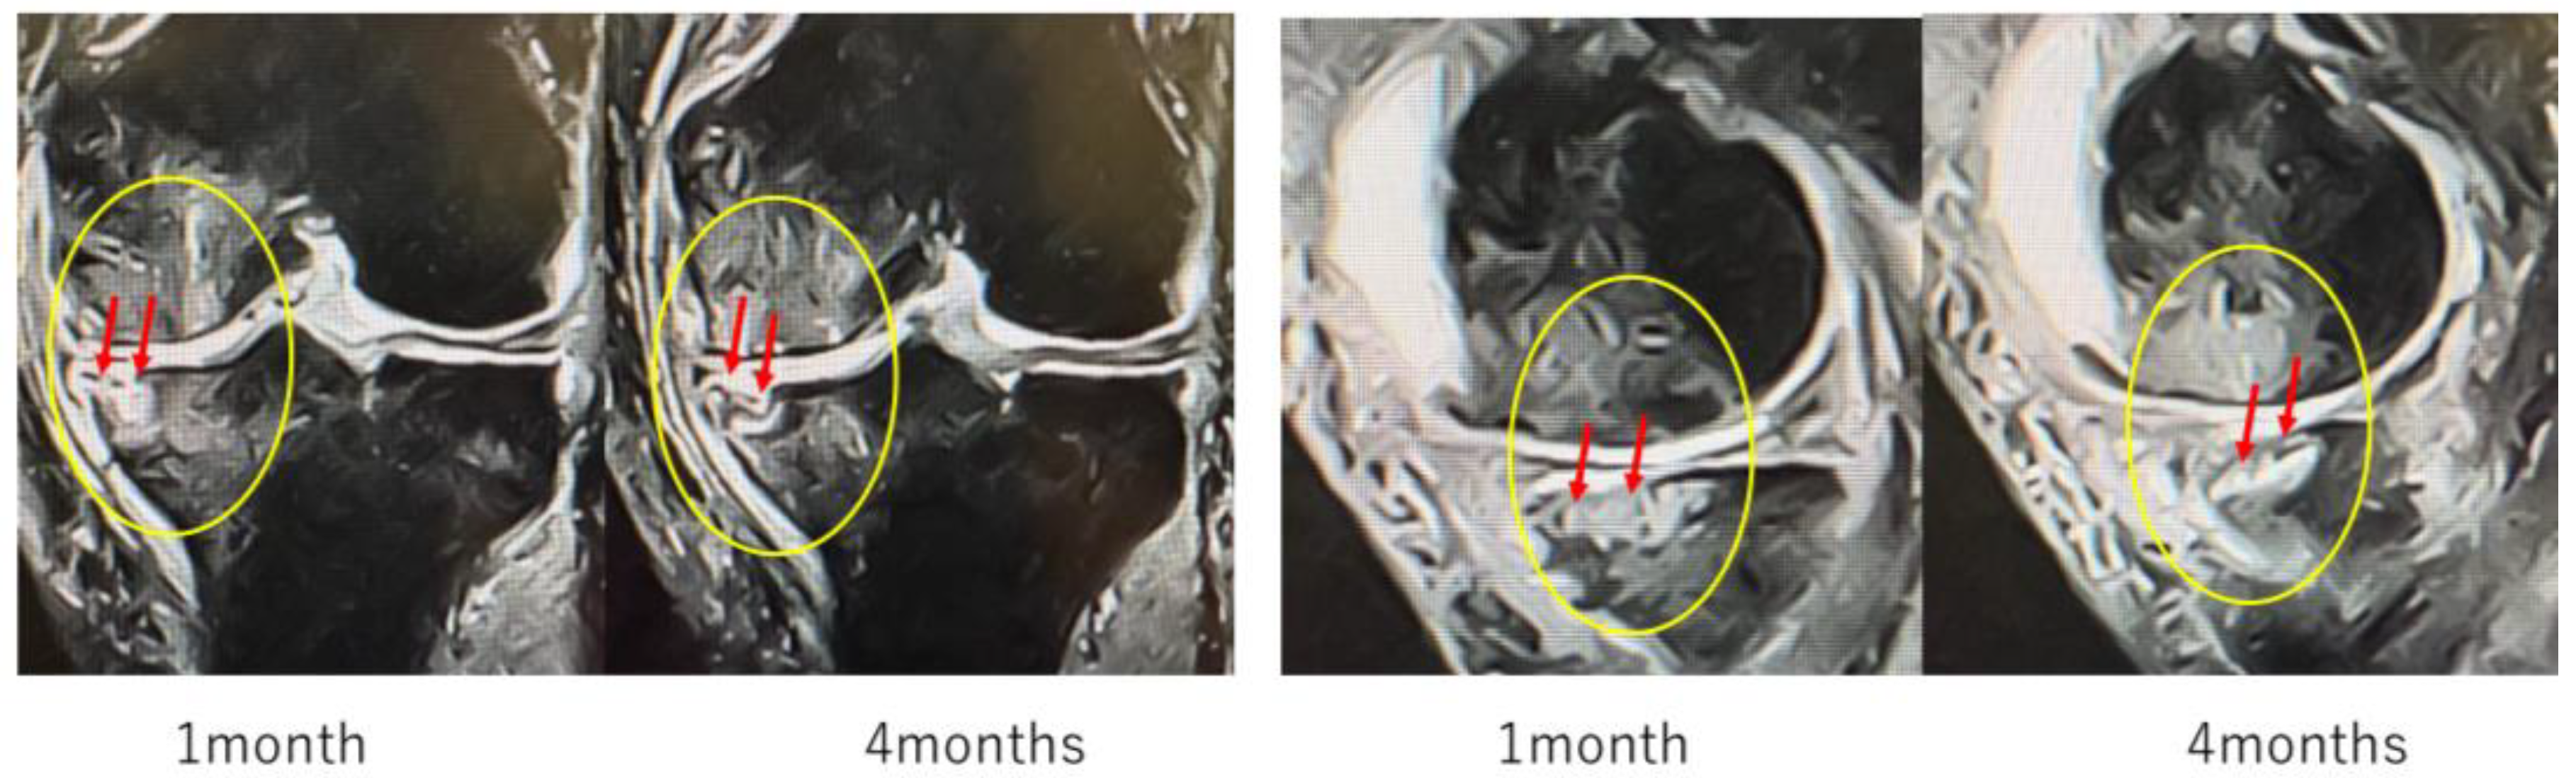

Figure 10 (Case 5) shows T2-weighted MRI findings at 1 and 4 months after intraosseous MSC administration. In sagittal and coronal views, progressive subchondral bone collapse and depression of the articular surface were observed, which became more pronounced between 1 and 4 months. These morphological changes were accompanied by alterations in joint congruity, suggesting ongoing structural compromise that may predispose to secondary osteoarthritic changes.

Figure 10.

Progression of subchondral bone collapse after intraosseous MSC administration (T2-weighted images). MRI scans at 1 month and 4 months post-treatment. The left images show sagittal views, and the right images show coronal views. Yellow circles and red arrows indicate progressive subchondral bone collapse and depression of the articular surface from 1–4 months. In cases with extensive BML near the articular surface, MSC administration may increase bone fragility, necessitating cautious rehabilitation and load management.

Particularly in cases with extensive BML located adjacent to the articular surface, MSC administration may increase bone fragility, indicating the need for careful rehabilitation and load management.